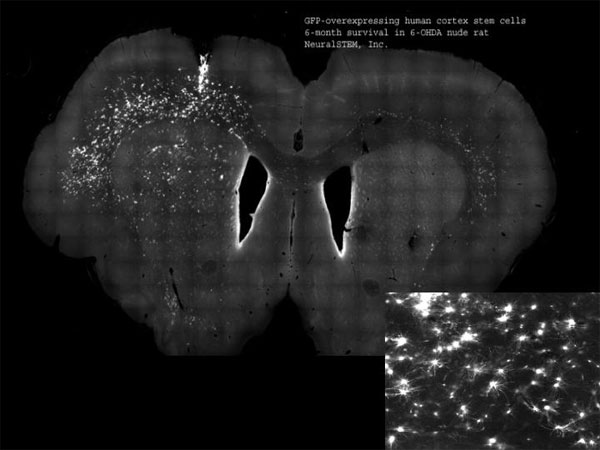

According to Neuralstem's press release, the patent issuing from the '352 application will cover methods of immortalizing any human neural stem cell using c-Myc-ER, a fusion protein of c-Myc and estrogen receptor (ER). The immortalized human neural stem cells can be grown for over 60 cell doublings. The claimed methods will allow for the production of commercial quantities of neural stem cells of the human brain and spinal cord, which can then be differentiated into human neurons and glia (a video of Neuralstem's process can be viewed here). Stable neural stem cells produced by the claimed methods can be used to treat diseases of the major central nervous system, including ischemic spastic paraplegia, traumatic spinal cord injury, Huntington's disease, and amyotrophic lateral sclerosis (ALS). In December, Neuralstem filed an IND application for ALS clinical trials using its stable neural stem cells, after showing in preclinical studies that the cells extended the life of rats with ALS.